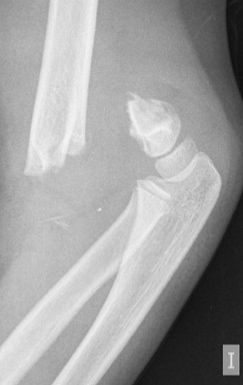

Figura 8: a-d, Imagen radiografica de fractura del cóndilo lateral con desplazamiento articular. Tratamiento quirúrgico mediante reducción abierta y osteosíntesis.